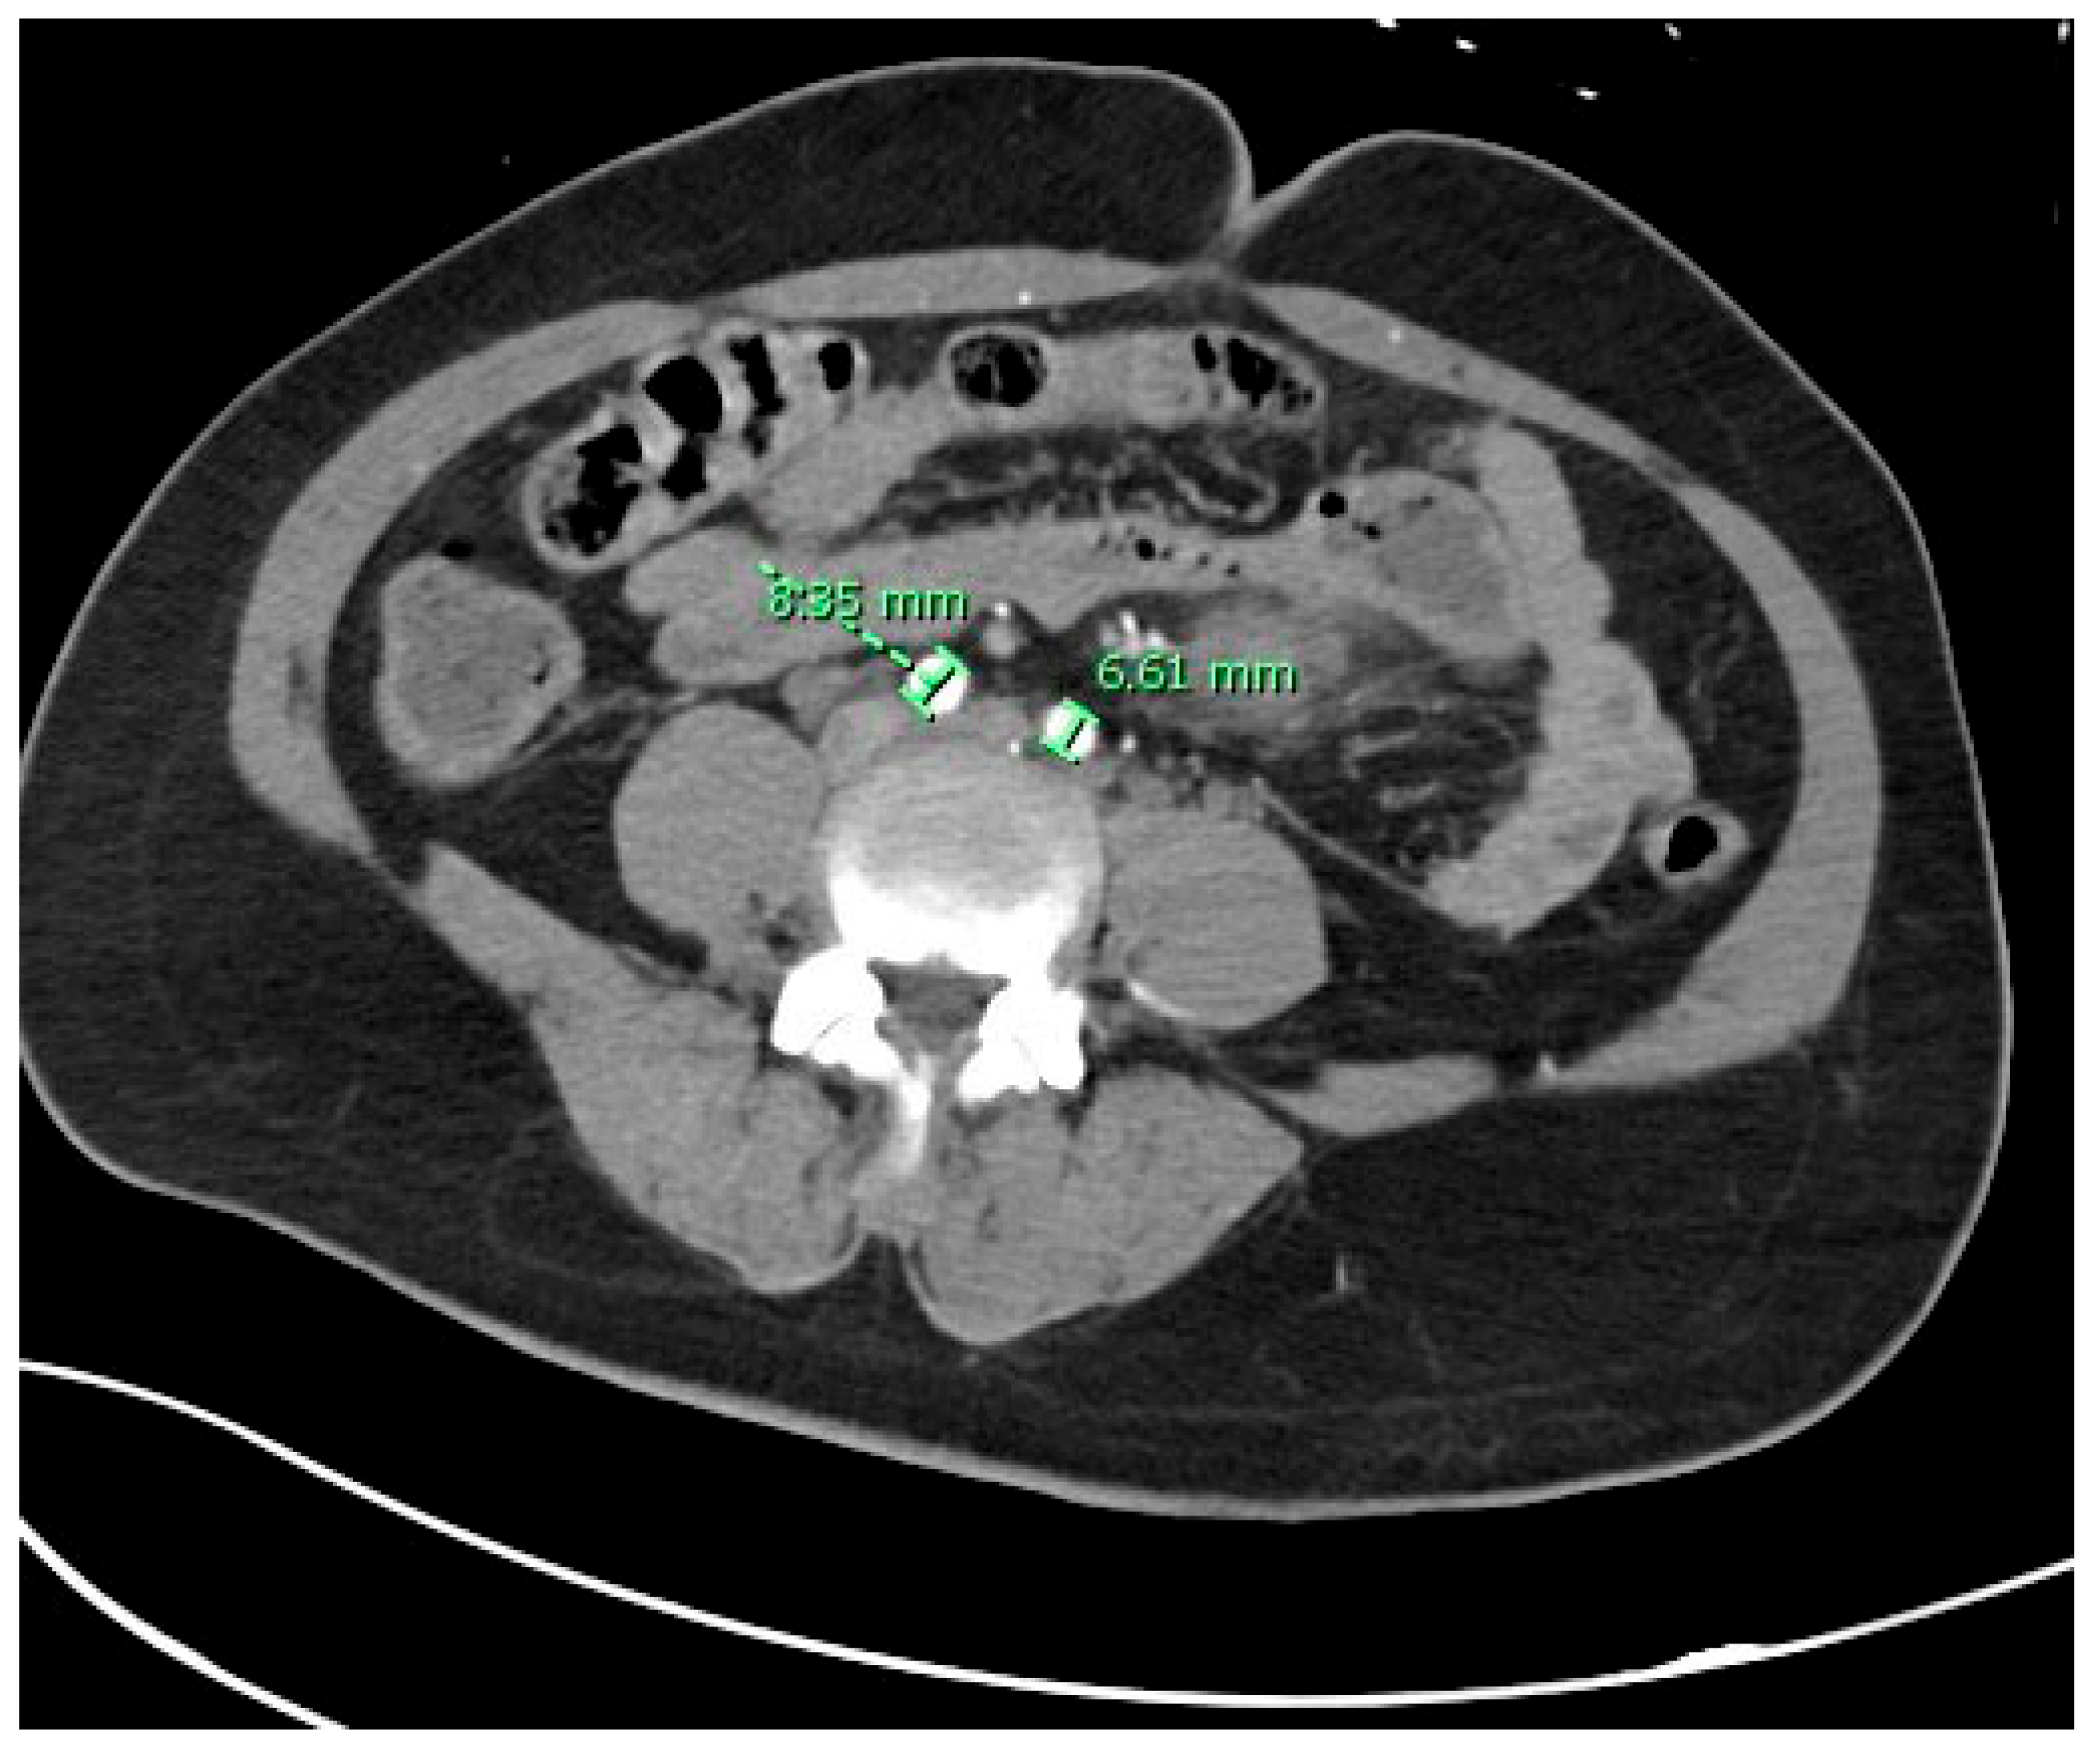

Level of Abdominal Aorta Bifurcation and Its Relation to the Ureter: A Radiological Study with Clinical Implications

3. Results